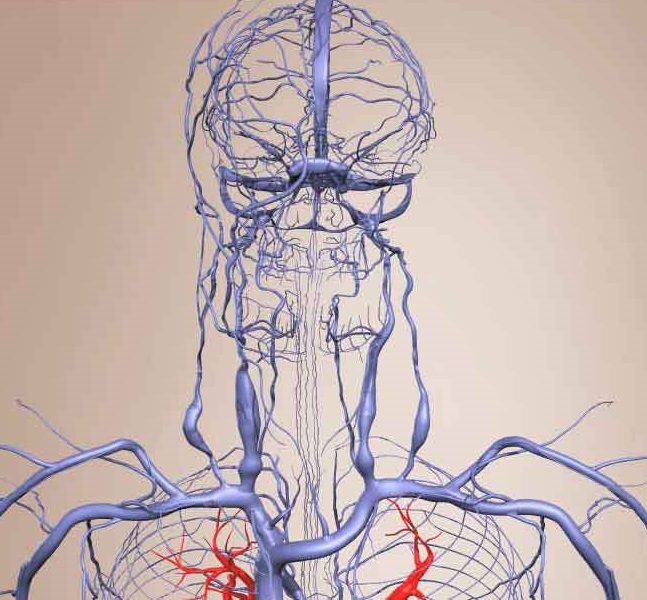

Анатомия внутренней яремной вены: КТ изображения